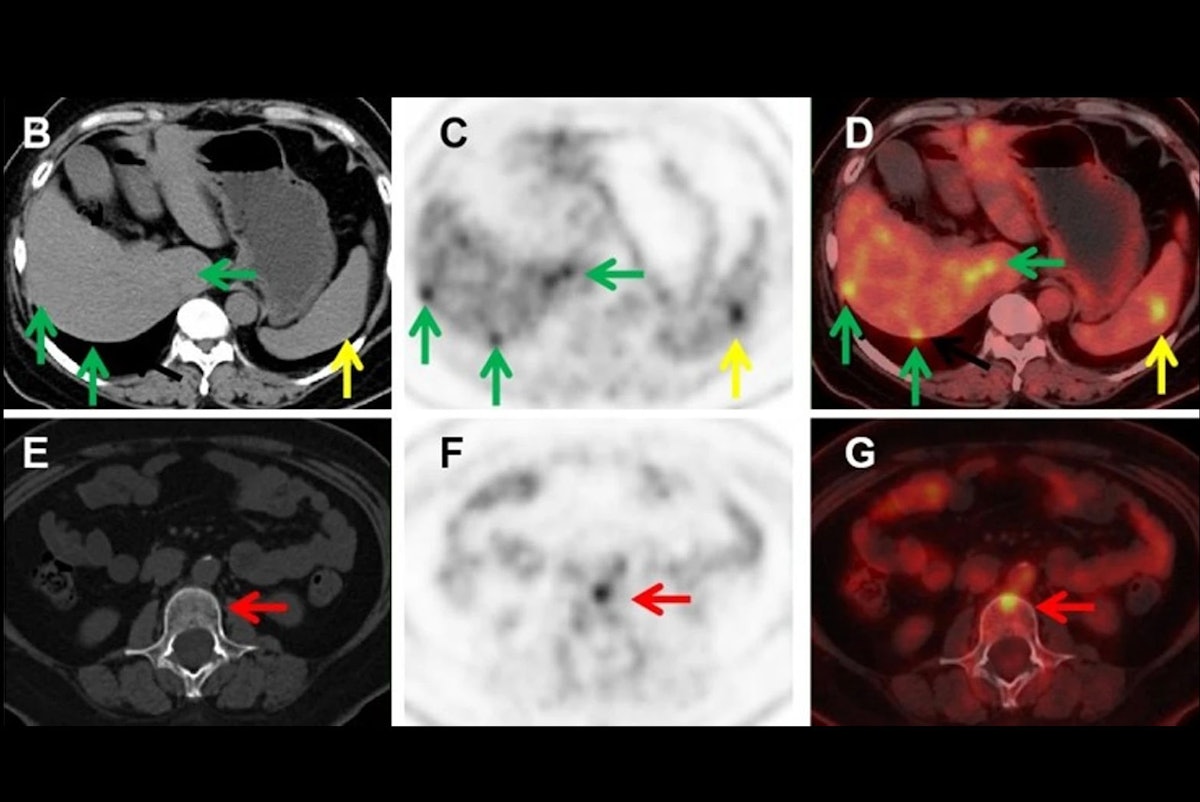

F-18 FDG-PET/CT may be a useful diagnostic tool for detecting metastatic uveal melanoma, researchers have reported.

The finding is from a retrospective analysis of imaging results from 55 participants and suggests that F-18 FDG-PET/CT can play a…